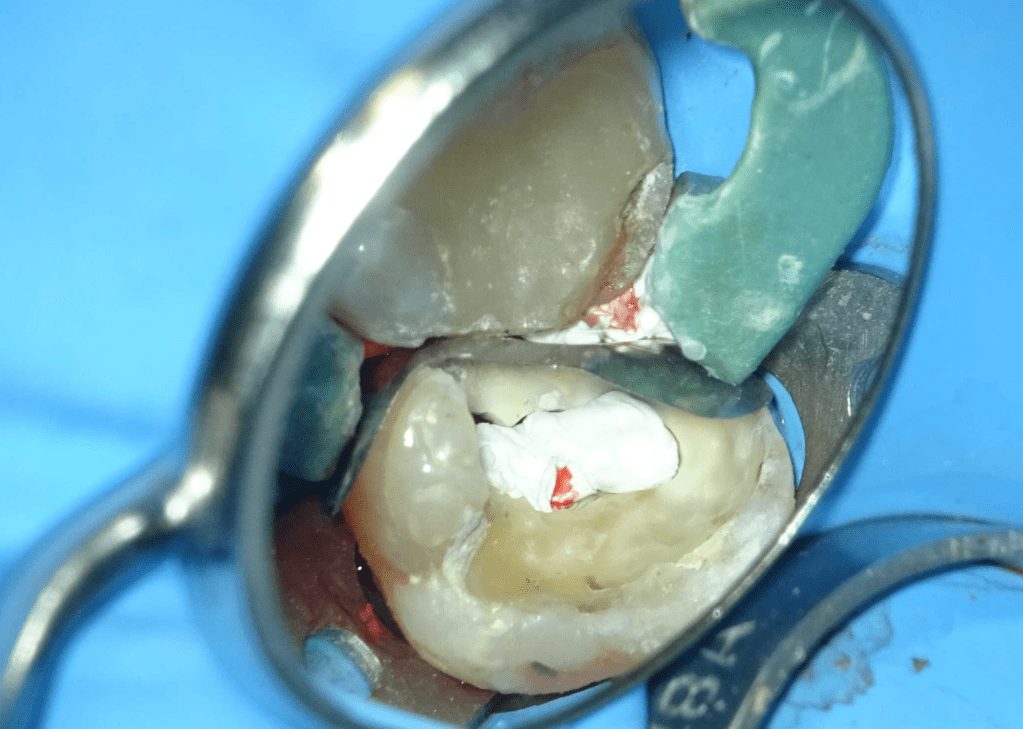

Pulpotomía biodentine + reco preendio